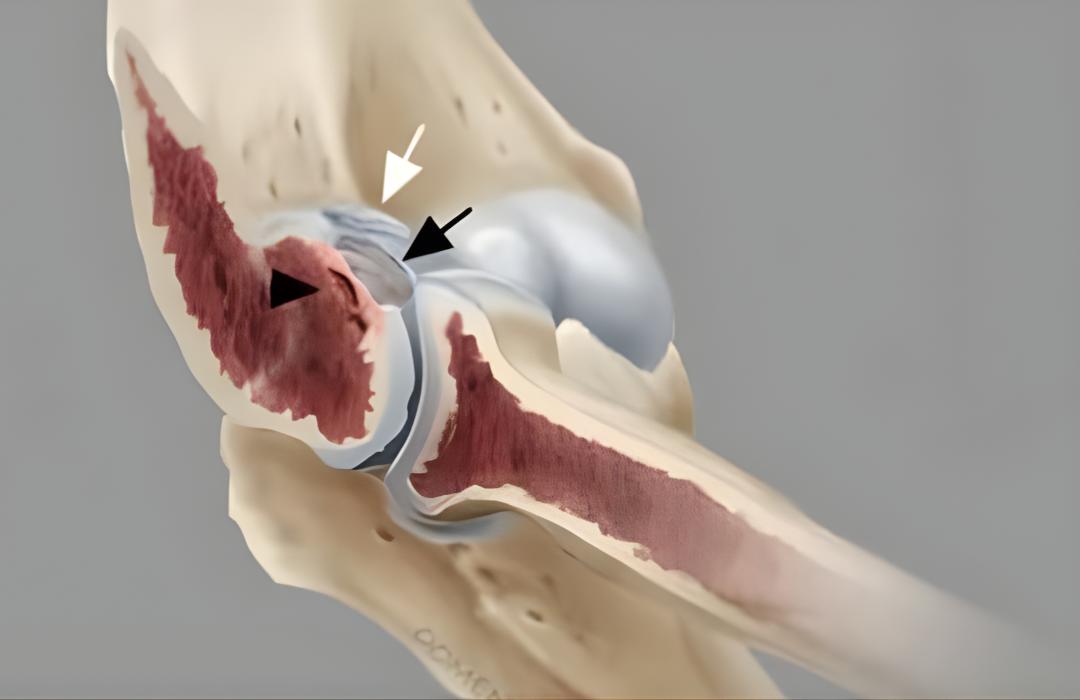

A osteocondrite dissecante é uma condição em que um fragmento de cartilagem e osso subjacente perde sua conexão com o restante da articulação, geralmente devido à falta de irrigação adequada. Isso causa dor, estalos, travamentos e sensação de instabilidade.

Acredita-se que a condição esteja relacionada à falta de irrigação sanguínea adequada em uma área do osso, microtraumas repetitivos, fatores genéticos ou sobrecarga articular.

Dependendo do caso, pode ser feita a fixação do fragmento com pinos, a remoção do fragmento solto, a estimulação da cartilagem por microfraturas ou técnicas de transplante osteocondral.